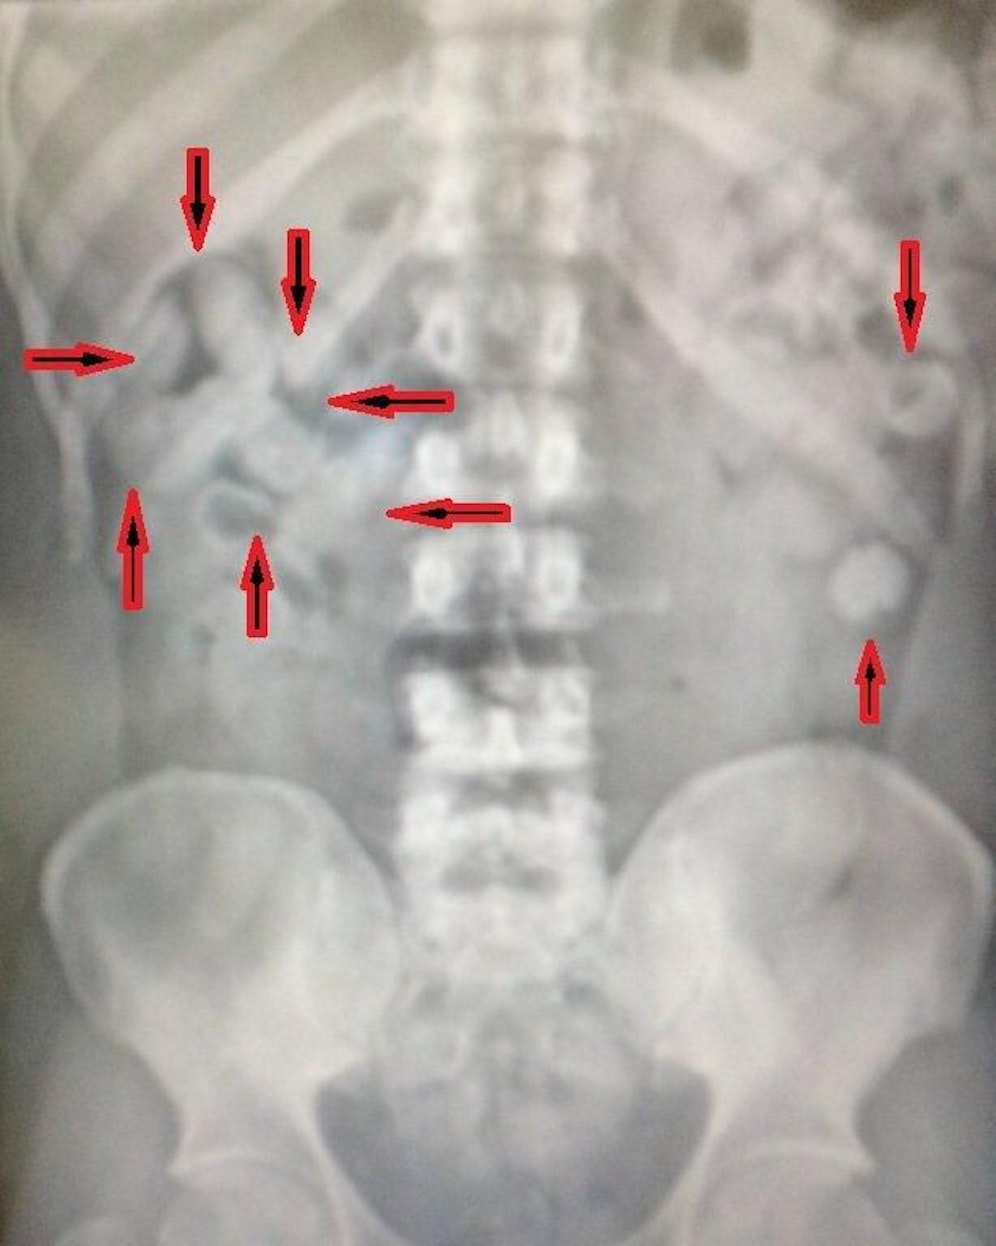

Riesenerfolg für Drogenfahnder in Simmering! Kriminalbeamte konnten einen 42-Jährigen festnehmen, der 107 Bodypacks verschluckt hatte. Das Kokain, insgesamt 1,2 Kilogramm, hat einen Wiederverkaufswert von zumindest 150.000 Euro.

Bei einer Personsdurchsuchung wurden neun Packerl Koakin in der Kleidung gefunden, doch das weit größere Drogenreservat verbarg sich im Körperinneren. 107(!) weitere Bodypacks, insgesamt 1.200 Gramm, wurden gefunden. Der Wiederverkaufswert des Schtgifts beträgt 150.000 Euro.